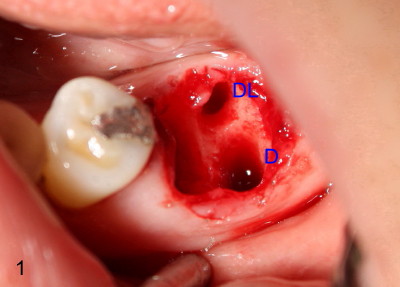

As discussed before, we plan to extract the affected tooth atraumatically by sectioning. When the distal portion of the tooth is taken out, there are two sockets distally (D, DL in Fig.1). There is an extra distal root (arrowhead in Fig.2). The mesial (M) and distal (D) portions of the tooth are laid out so that the buccal (B) is placed outside, lingual (L) inside of the photo. We are seeing the sectioned surfaces of the tooth. With the same arrangement, PA is taken (Fig.3). The silver cone (black arrowheads) is off the center of the mesial root, suggesting missing mesiolingual canal. The second missing canal, distolingual (blue arrowheads) is narrow and highly curvy. In fact the mesiolingual canal is also obliterated. It takes effort and time to go through it (Fig.4 black arrowhead). The distolingual canal is so obliterated that perforation is the end result (using rotary file) (blue arrowheads).